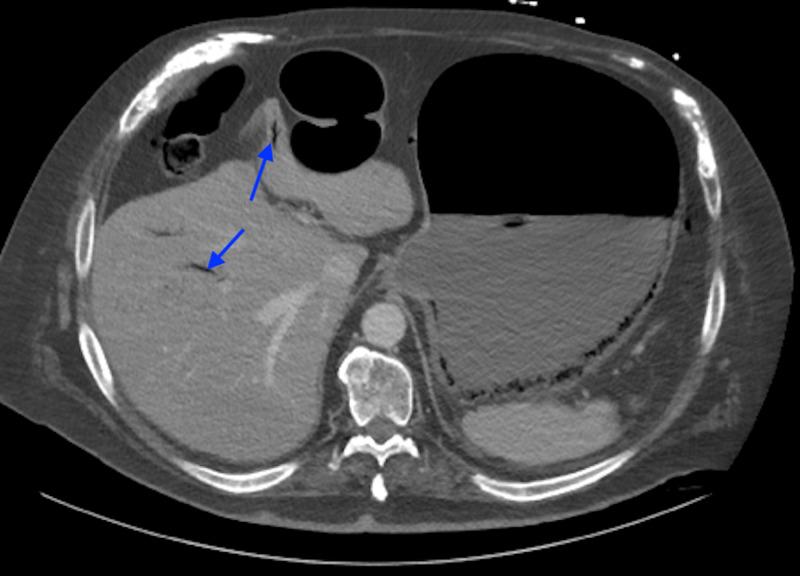

Gastric Ischemia Secondary to Abdominal Distension.

Gastric ischemia has been reported in the literature mainly as case reports and case series. It is uncommon because of its excellent blood supply. Patients with atherosclerosis and vascular insufficiency are at risk for gastric ischemia, especially with gastric distension. Workup may reveal radiographic findings that denote ischemia and would prompt surgical intervention. However, these patients with vascular insufficiency tend to be poor surgical candidates, which can present a dilemma. The authors report two cases where non-operative management for gastric ischemia was successfully accomplished.